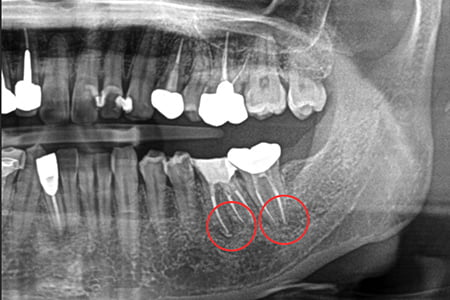

治療例2

| 症状 | 左下奥歯が噛むと違和感がある |

|---|---|

| 治療方針 | 歯根嚢胞を認め歯が保存可能か分析。保存可能であれば根管充填及びファイバーコア、補綴修復を行う |

| 治療期間 | 1年9カ月 |

| 治療費用(税込) | ¥666,600 ※2歯分 |